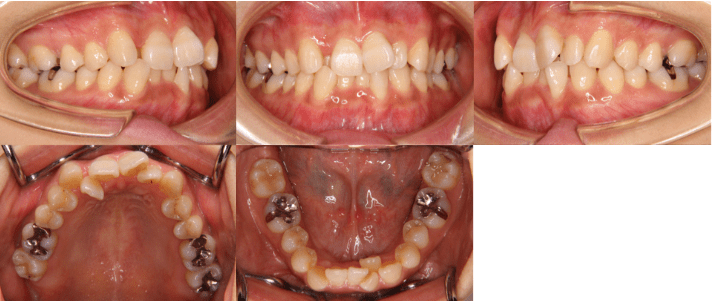

治療前

• 初診時年齢:25歳7ヶ月

• 主訴:前歯のガタガタ

• 診断:交叉咬合を伴う叢生症例

• 治療内容:小臼歯4本を抜歯した後、マウスピース型カスタムメイド矯正歯科装置(製品名インビザライン 完成物薬機法対象外)を使用して主訴である叢生の改善を行いました。

• 治療期間:2年

• リスク:矯正治療による歯の移動に伴う痛み、歯根吸収、虫歯

• 費用:80万円